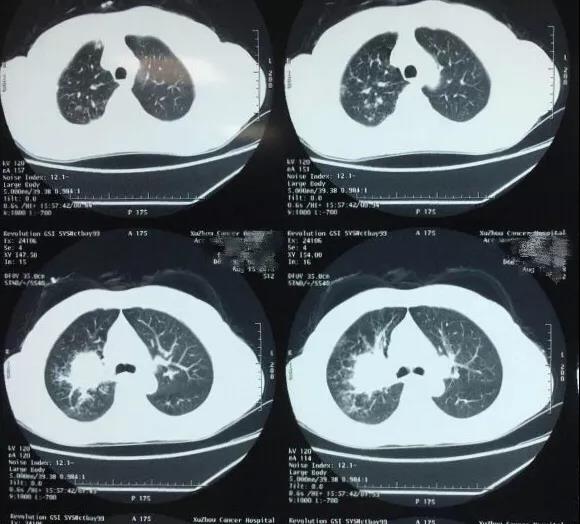

于是(shì),侯予龍博士立即對(duì)馮女(nǚ)士展開(kāi)了(le)進一步全身(shēn)腫瘤排查,檢查顯示馮女(nǚ)士左肺上(shàng)葉與右肺上(®shàng)葉皆有(yǒu)病竈,左側上(shàng)葉病竈較為(wèi)典型,右肺稍小(xiǎo)。病人(rén)患慢(màn)性肺氣管•炎、慢(màn)性肺氣腫、肥胖症,且心肺功能(néng)非常差,若同期進入雙側胸腔手術(shù),手術(shù)時(shí)間$(jiān)較長(cháng)、風(fēng)險也(yě)會(huì)增加。結合年(nián)齡與身(shēn)體(tǐ)因素,綜合評定後,侯予龍博士團隊建議(yì)患者,右肺随診觀察,先處理(lǐ)左側病竈,進行(xíng)“單孔胸腔鏡左上(shàng)肺癌根治手術(shù)”。